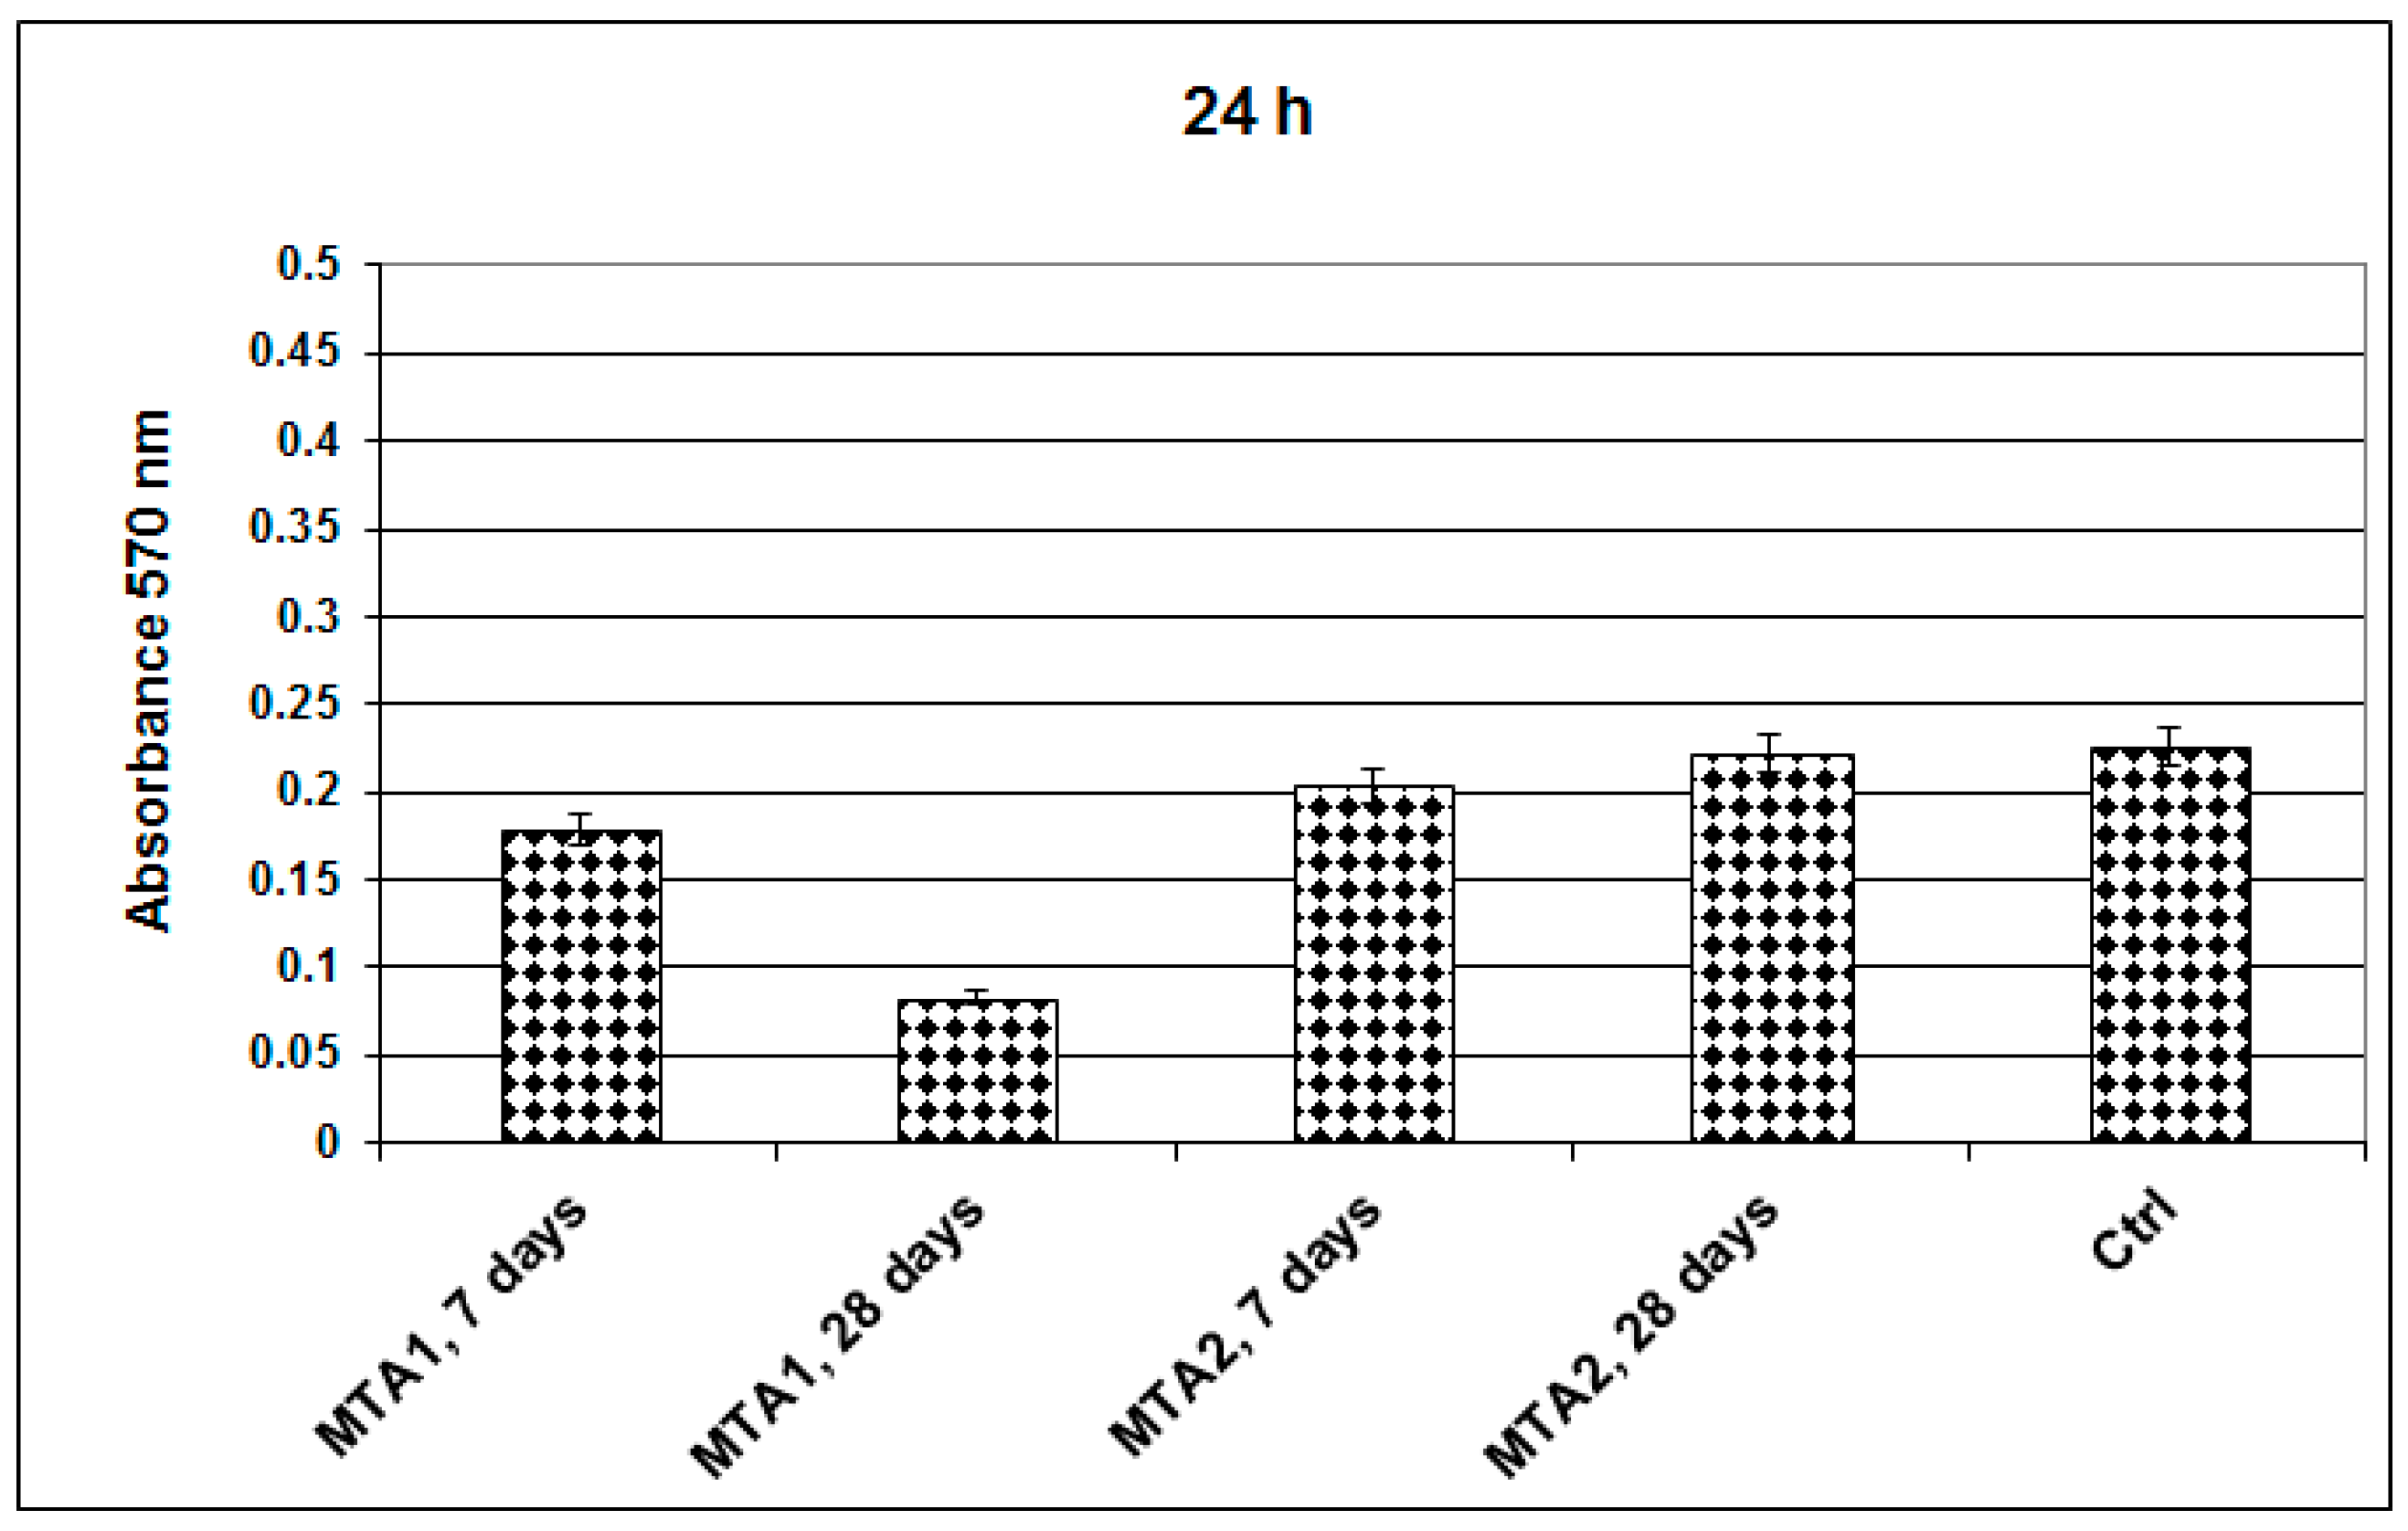

- MTT assay